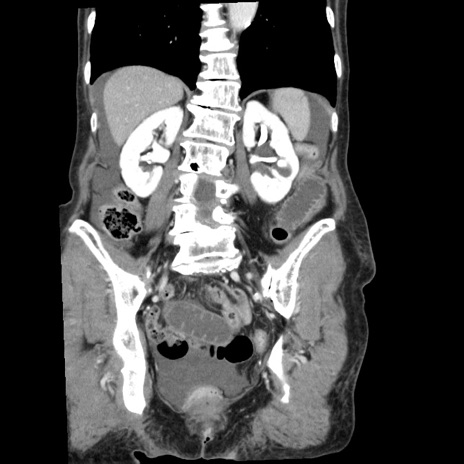

症例1(冠状断像)

【症例】80歳代女性

【主訴】腹痛

【現病歴】8時間前から腹痛あり来院。

【既往歴】糖尿病、脂質異常症、子宮体癌にて子宮全摘術

【身体所見】意識清明・会話良好だが腹痛で苦悶様、全腹部にわたって反跳痛と圧痛あり

【データ】WBC 13600、CRP 0.14、LDH 224、CK 90